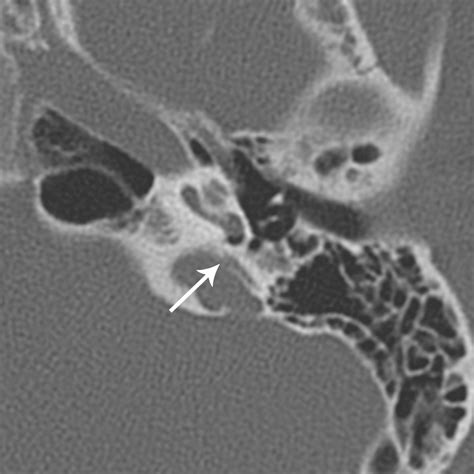

Diagnosing Semicircular Canal Dehiscence requires a combination of clinical history and specialized imaging. Because the opening in the bone is often microscopic, standard imaging may not be sufficient. Physicians typically rely on specific protocols to confirm the presence of the dehiscence.

High-Resolution CT (HRCT) Visualizing the temporal bone to identify the specific site of the dehiscence.